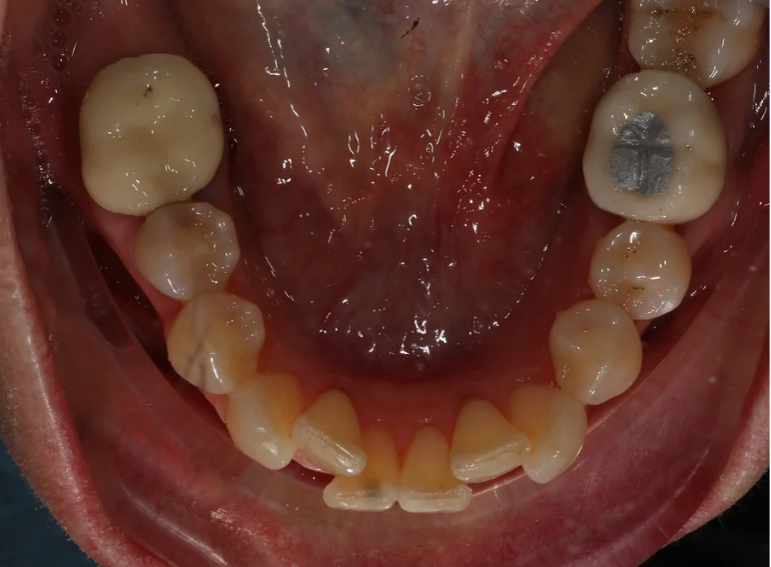

Root canal treatment and combined internal and external whitening.